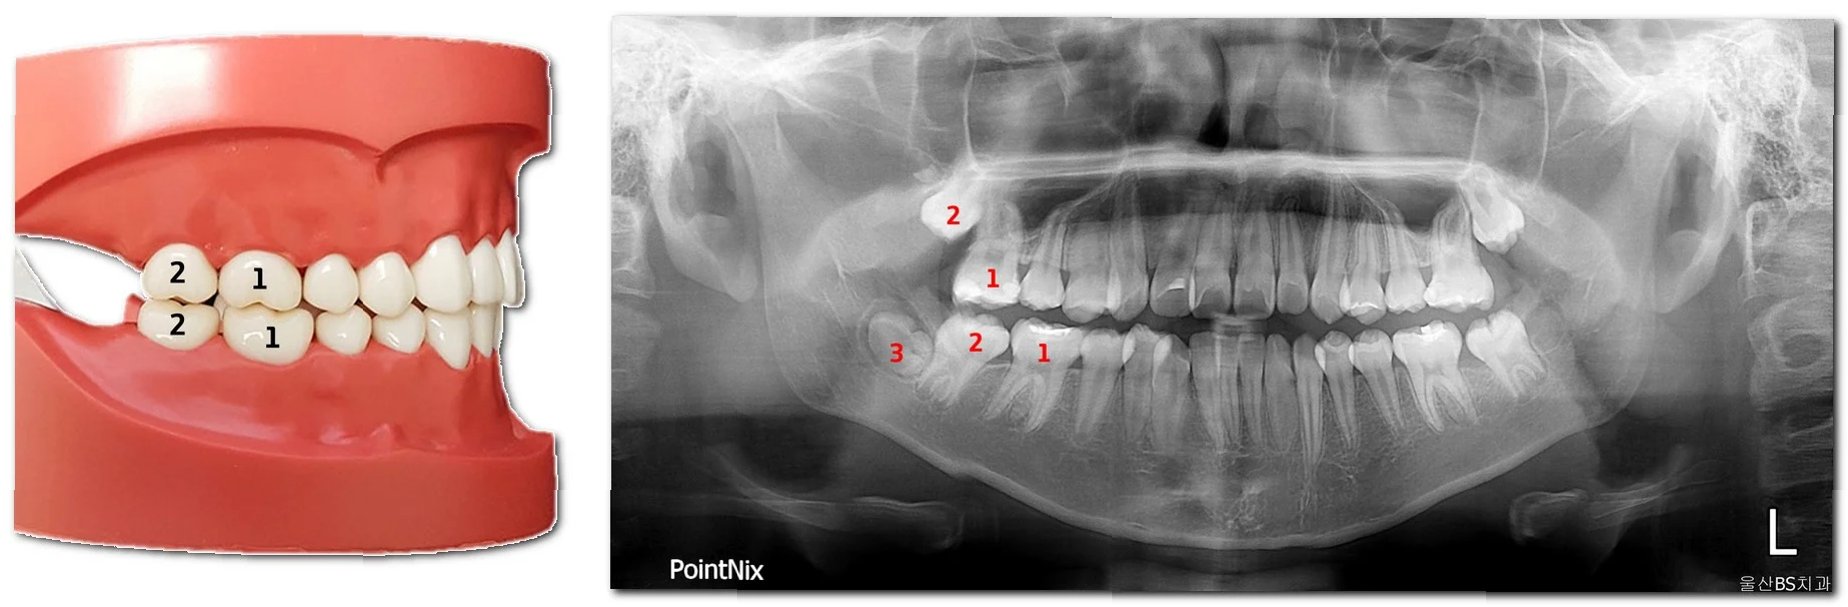

치아 맹출 지연이란, 예상되는 시기보다 치아가 늦게 나오는 경우를 말합니다. 유치의 경우, 생후 6개월에서 12개월 사이에 첫 번째 치아가 나오기 시작하여 3세 무렵에 20개의 유치가 모두 맹출하는 것이 일반적입니다. 영구치는 만 6세 전후로 나오기 시작하여 12세 전후로 모든 영구치가 맹출합니다. 하지만, 개인차가 존재하기 때문에, 맹출 시기가 조금 늦어진다고 해서 무조건 문제가 있는 것은 아닙니다. 하지만, 맹출이 지나치게 늦어지거나, 다른 증상(구강 위생 불량, 잇몸 염증 등)이 동반된다면 치과 검진을 통해 정확한 원인을 파악하고 적절한 조치를 취해야 합니다.

이소 맹출은 치아가 정상적인 위치에서 벗어나 다른 부위에 맹출하는 현상을 의미합니다. 이는 다양한 원인에 의해 발생할 수 있으며, 덧니, 매복치, 유치 잔존 등의 형태로 나타날 수 있습니다. 이소 맹출은 심미적인 문제뿐만 아니라, 잇몸 염증, 충치 발생 위험 증가, 턱관절 장애 등을 유발할 수 있으므로, 조기에 발견하여 적절한 치료를 받는 것이 중요합니다. 특히, 영구치가 맹출하는 과정에서 이소 맹출이 발생할 경우, 치아 배열에 심각한 영향을 미칠 수 있으므로 주의 깊게 관찰해야 합니다.

치아 맹출 지연과 이소 맹출의 원인은 다양합니다. 유전적인 요인, 영양 불균형, 내분비 질환, 외상, 치아 맹출 공간 부족, 턱뼈의 성장 부진 등이 원인으로 작용할 수 있습니다. 특히, 턱뼈의 성장 부진은 치아 맹출 공간 부족을 유발하여 이소 맹출의 주요 원인이 될 수 있습니다. 젖니를 너무 일찍 상실하거나, 충치로 인해 치아를 일찍 발치한 경우에도 주변 치아가 빈 공간으로 이동하면서 영구치 맹출 공간이 부족해져 이소 맹출이 발생할 수 있습니다. 따라서, 정기적인 치과 검진을 통해 아이의 구강 상태를 꼼꼼하게 확인하고, 필요한 경우 예방적인 치료를 받는 것이 중요합니다.